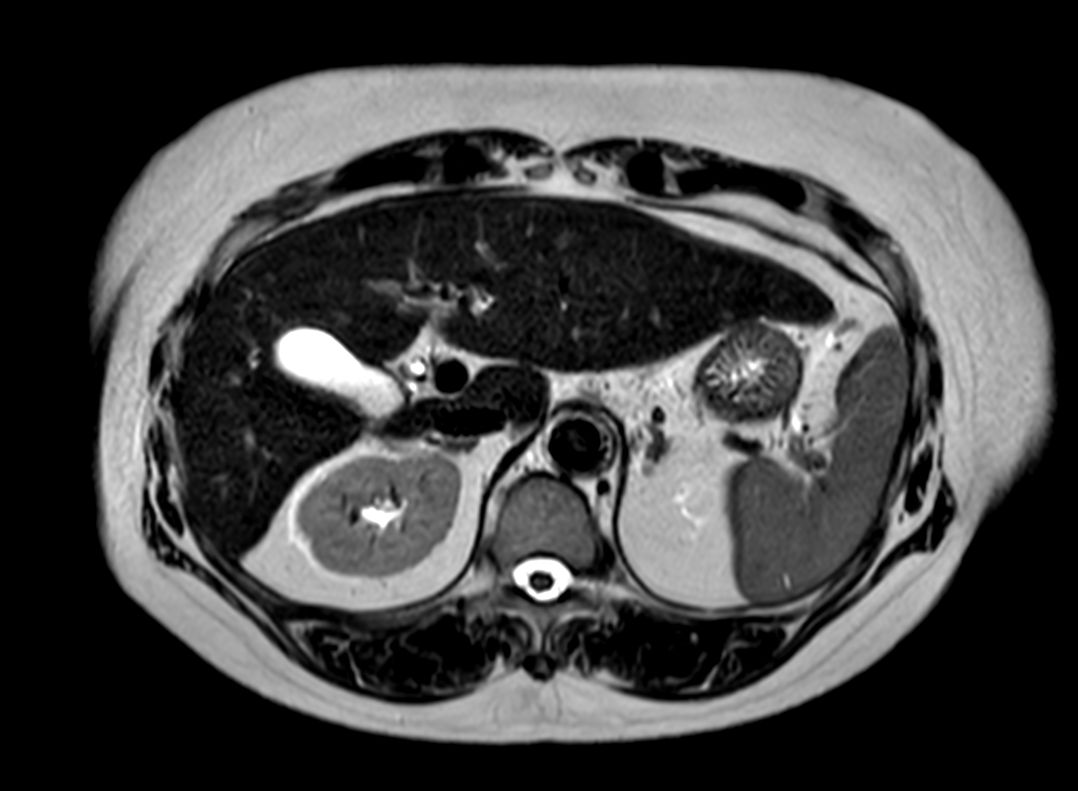

T1w FFE (In Phase)

T1w FFE (Out Phase)

Diffusion (b0)

Diffusion (b1000)

Diffusion (ADC)